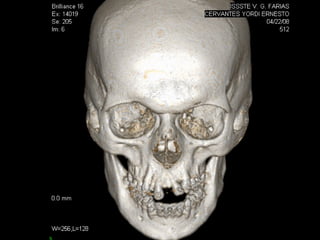

Tomografía computarizada

De seno maxilar corte sagital.

Area de implantación

Dentaria.

Material osteoconductor

para elevar el piso antral

Nuevo piso del seno y su

margen de seguridad para

contener el implante

Uno de los fenómenos fisiológicos más comunes es la falta de hueso en el

Piso del antro de Highmore, secundario a la neumatización de los senos y

Que en muchas ocasiones aproxima el piso antral al proceso alveolar, por

Lo que sobre todo en pacientes jóvenes es factible dar volumen a este

Área con la aplicación de injerto de hueso humano, equino o derivados de

arcillas de sílice. Las indicaciones de usar uno u otros depende de la experiencia

Clínica del operador.